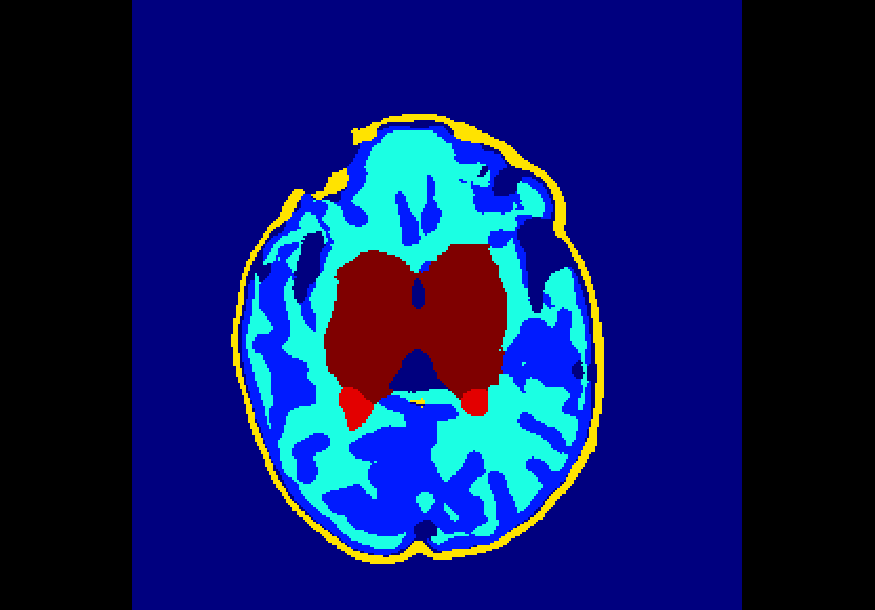

The dataset consisted of 70 3D T2-weighted brain MRI scans publicly available from the dHCP neonatal cohort. The segmentation maps had 10 classes, corresponding to: zero-pixel background, cerebrospinal fluid (CSF), cortical grey matter (cGM), white matter (WM), background bordering brain tissues, ventricles, cerebellum, deep grey matter (dGM), brainstem, and hippocampus. The scans covered an age range of 24.3-42.2 weeks. The data was available in NIfTI format; Figure 1 shows an example scan and corresponding tissue labels. We carried out a pre-processing step where each scan was independently normalised to zero-mean and unit-variance.

Finally, Table 4 shows that the model trained on data injected with different degrees of both Gaussian and salt-and-pepper noise (gaus01, gaus03, gaus04 with = 1, 3, 4 ; snp01, snp05, snp10 with prob = 0.01, 0.05, 0.10) achieves the best overall robustness across the 16 versions of the test set, where even the heaviest filtered images had very few segmentation inaccuracies. For instance, this model demonstrated high levels of robustness on all 10 classes for noise-free data, on data injected with a previously unseen degree of salt-and-pepper noise (e.g. DSCs of 88%-99% on snp20), as well as on data with a previously unseen degree of Gaussian noise (e.g. DSCs of 72%-98% on gaus05). To illustrate, Figure 5 shows examples of the predicted segmentation of the model on the heaviest transformed images of the three filter categories used in these experiments. From the figure it is clear that the model achieved excellent mapping of the brain tissue regions. This shows a tremendous improvement from the baseline model which was trained using a conventional, noise-free approach and thus failed severely on the heavily corrupted images (e.g. DSCs of 0% for all 10 classes on snp20, see Table 2).